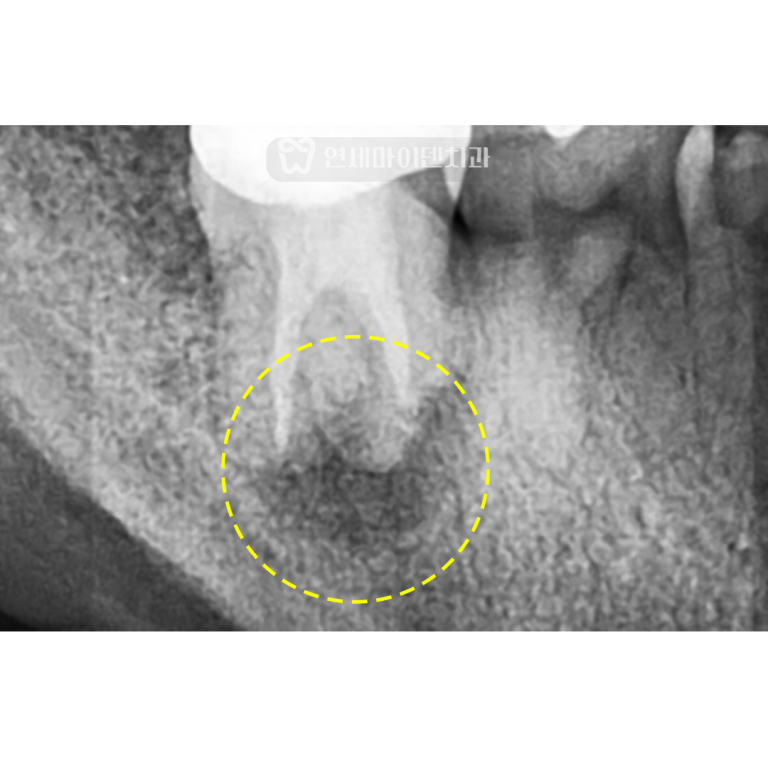

아들의 영구치를 살려주신 남택진 원장님과너무나도 친절하게 살펴주신 간호사 선생님들께진심으로 감사드립니다. 누워서 매립된 어금니 밑으로 큰 낭종이…

재신경치료&임플란트 증례: 잇몸 여드름 신경치료 후에도 치아 뿌리에 염증이 생기고,잇몸에 여드름 같은 고름 주머니가 올라오면,대부분 ‘발치해야…

안녕하세요, 소중한 치아를 지키는연세마이덴치과 닥터꼬집입니다. 많은 분들이 신경치료 후 염증이 재발했을 때,재신경치료를 시도할지, 임플란트로 바로 가는게…